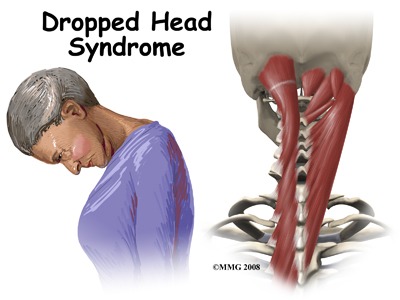

What Is Dropped Head Syndrome?

Dropped Head Syndrome is a medical condition characterized by severe weakness in the neck extensor muscles, making it difficult for individuals to keep their head upright. Over time, the head may tilt forward, with the chin resting near the chest. This condition can significantly impact a person’s quality of life by limiting mobility, communication, and even breathing in severe cases. Although the condition is rare, understanding its causes and symptoms is important—especially as it can be confused with more common posture-related or muscular issues.

DHS is most often linked to neuromuscular disorders—conditions that affect the nerves and muscles, including: Myasthenia gravis, Amyotrophic lateral sclerosis (ALS), Parkinson’s disease, Multiple system atrophy, Inflammatory myopathies (such as polymyositis). In some rare cases, lifestyle factors and long-term physical strain may contribute to progressive muscular fatigue or postural imbalances. Individuals who experience prolonged periods of poor posture, untreated back or neck discomfort, or nutritional imbalances may place additional stress on spinal muscles, which over time may contribute to abnormal curvature or muscle atrophy. In the case highlighted by doctors, no trauma or structural damage to the cervical spine was identified, suggesting that muscular degeneration and neuromuscular dysfunction were at the core of the diagnosis.